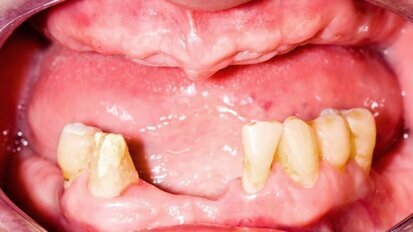

Raziskovalci so odkrili morebitne biomarkerje za zobno gnilobo

Odense, Danska / VALENCIA, Španija: Za določitev potencialnih biomarkerjev za zobno gnilobo, je mednarodna skupina raziskovalcev podrobneje raziskala ...

Izguba zob je lahko povezana z nižjo kognitivno funkcijo

Chapel Hill, NC, ZDA: Ameriški raziskovalci, ki ugotavljajo, v kolikšni meri je oralno zdravje povezano s kognitivnim statusom, menijo, da sta...